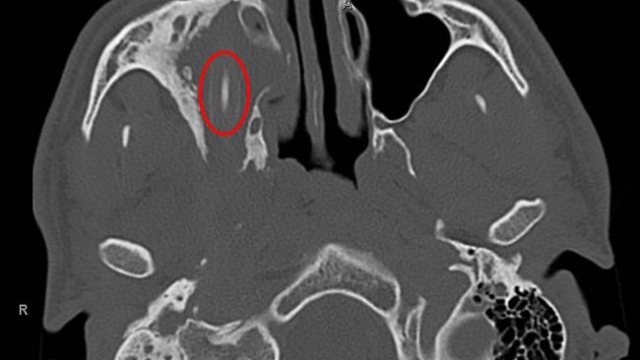

Aachen University Hospital says the 24-year-old man sought help in 2011 after suffering for years from headaches, constant colds and worsening vision in one eye. A scan showed that a four-inch pencil was lodged from his sinus to his pharynx and had injured his right eye socket.